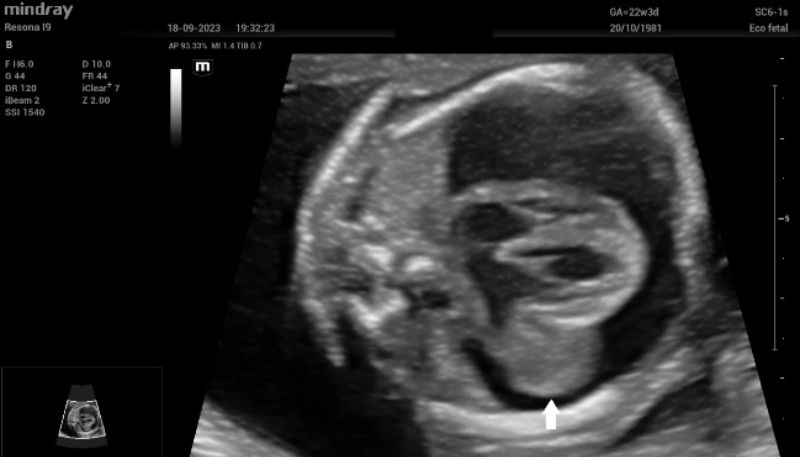

Upon admission, fetal echocardiography revealed a well-defined intrapericardial bilobed mass, measuring 20 mm x 16 mm x 10 mm, located in the free wall of the left atrium and left ventricle at the level of the mitral valve and presenting with severe pericardial effusion (Fig. 1).

Figure 1: Septal four-chamber view of the fetal heart. The teratoma (white arrow) is clearly seen at the level of the mitral valve.